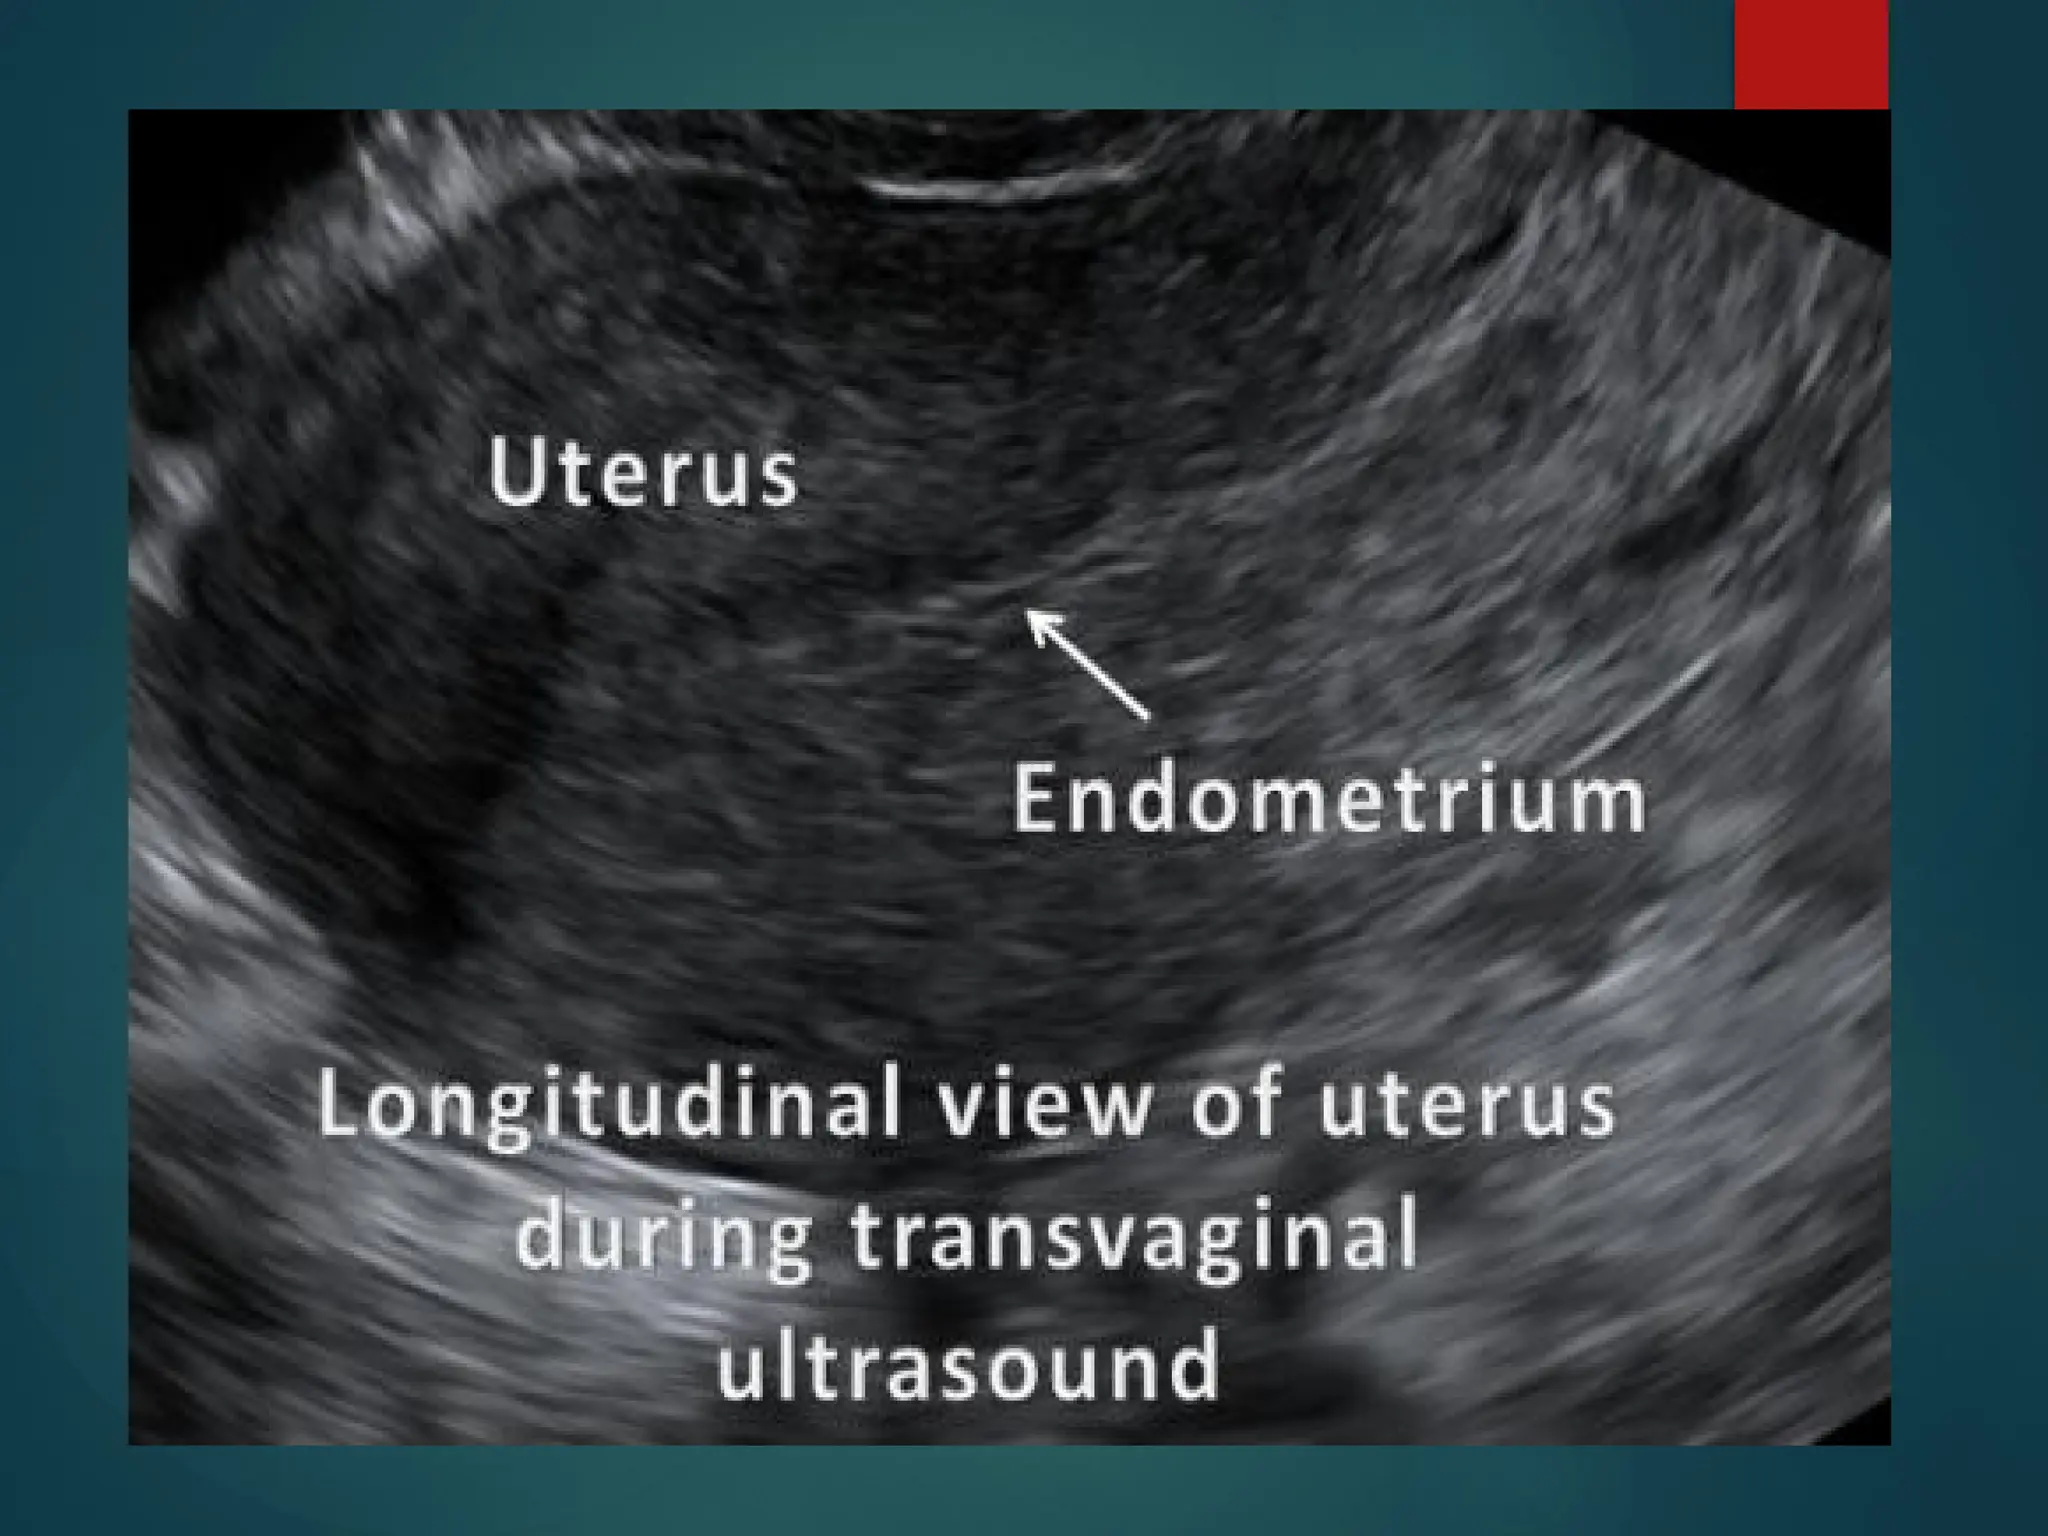

Trans Vaginal Ultrasound

(TVS)

 Method of choice for

 Monitoring infertility disorders

 Diagnosis of ectopic pregnancy

 Differentiation of normal and abnormal 1st

trimester pregnancy

 Diagnosis of congenital anomalies in 2nd

trimester

 Patient to have empty bladder because

 Uterus will be pushed posteriorly out of the field

of view of the transducer

Trans Vaginal Ultrasound (TVS)

cont

• Specially designed high frequency transducers

• Higher resolution images

• Favorable for obese patients or in early stage of

pregnancy

• Limitations include

– Reduced beam penetration

– More invasive nature of the technique